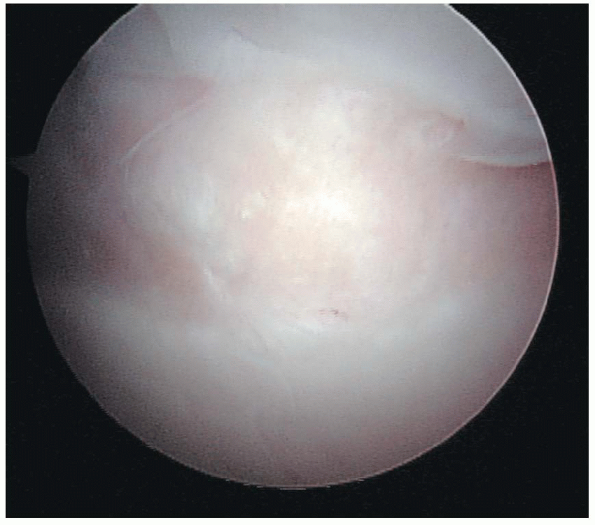

FIGURE 1-1.

The long head of the biceps tendon acts as a major landmark for orientation within the joint. When the patient is in the lateral decubitus position the biceps tendon is seen approximately 10 to 15 degrees from an imaginary vertical line. In the beachchair position, the tendon runs quite parallel to floor before it enters the bicipital groove. The tendon originates from the supraglenoid tubercle at the superior rim of the glenoid and from the superior, usually posterior, glenoid labrum. Variable sites of origin include the supraglenoid tubercle and either or both of the anterior and posterior labrum. |

is the first major structure that should be identified within the

glenohumeral joint, because it acts as a major landmark for orientation

within the joint. When the patient is in the lateral decubitus position

the biceps tendon is seen approximately 10 degrees to 15 degrees from

an imaginary vertical line. In the beachchair position, the tendon runs

quite parallel to floor before it enters the bicipital groove. The

tendon originates from the supraglenoid tubercle at the superior rim of

the glenoid and from the superior, usually posterior, glenoid labrum (Fig. 1-1).

However, it is important to note that the sites of origin are variable.

Studies have documented that 20% of normal biceps tendons attach only

to the supraglenoid tubercle; 48% only to the superior, posterior

glenoid labrum; and 28% originating from both points. To facilitate

visualization of the tendon as it courses anterolaterally through the

joint, the arm should be externally rotated. The tendon can be observed

as it exits into the bicipital groove, between the tendons of the

subscapularis and supraspinatus muscles. In the anatomic position, the

intraarticular portion of the biceps tendon courses below the

coracohumeral ligament, which strengthens the rotator interval, a space

between the tendons of the subscapularis and supraspinatus muscles. The

coracohumeral ligament and superior glenohumeral ligament aid in the

support of the biceps tendon in the rotator interval.